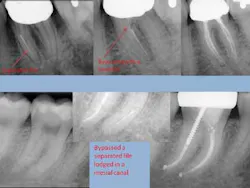

- Separated file — The dreaded separated file is probably the most common complication clinicians encounter when performing root canals. There was a time when those broken instruments made me wish I never started the root canal in the first place. These days, I will work to bypass the file and get a predictable result.

To prevent file fractures, irrigate after every file. Also, apply gentle pressure and never push when instrumenting a canal.

If a file separates, take a P.A. film immediately to figure out where in the canal the file is lodged. Most likely there’s a curve that the file could not negotiate. Start negotiating the canal with a 6 or 8 C-file. The goal is to engage the space around the file where you can instrument next to it. It could take an extra 30 or 40 minutes and lots of irrigation, but you should be able to negotiate the canal with a 15 file to working length. Irrigate very well and obturate. Sometimes the file will actually exit the orifice of the tooth when irrigating. But it’s perfectly reasonable to use the file as part of the fill.